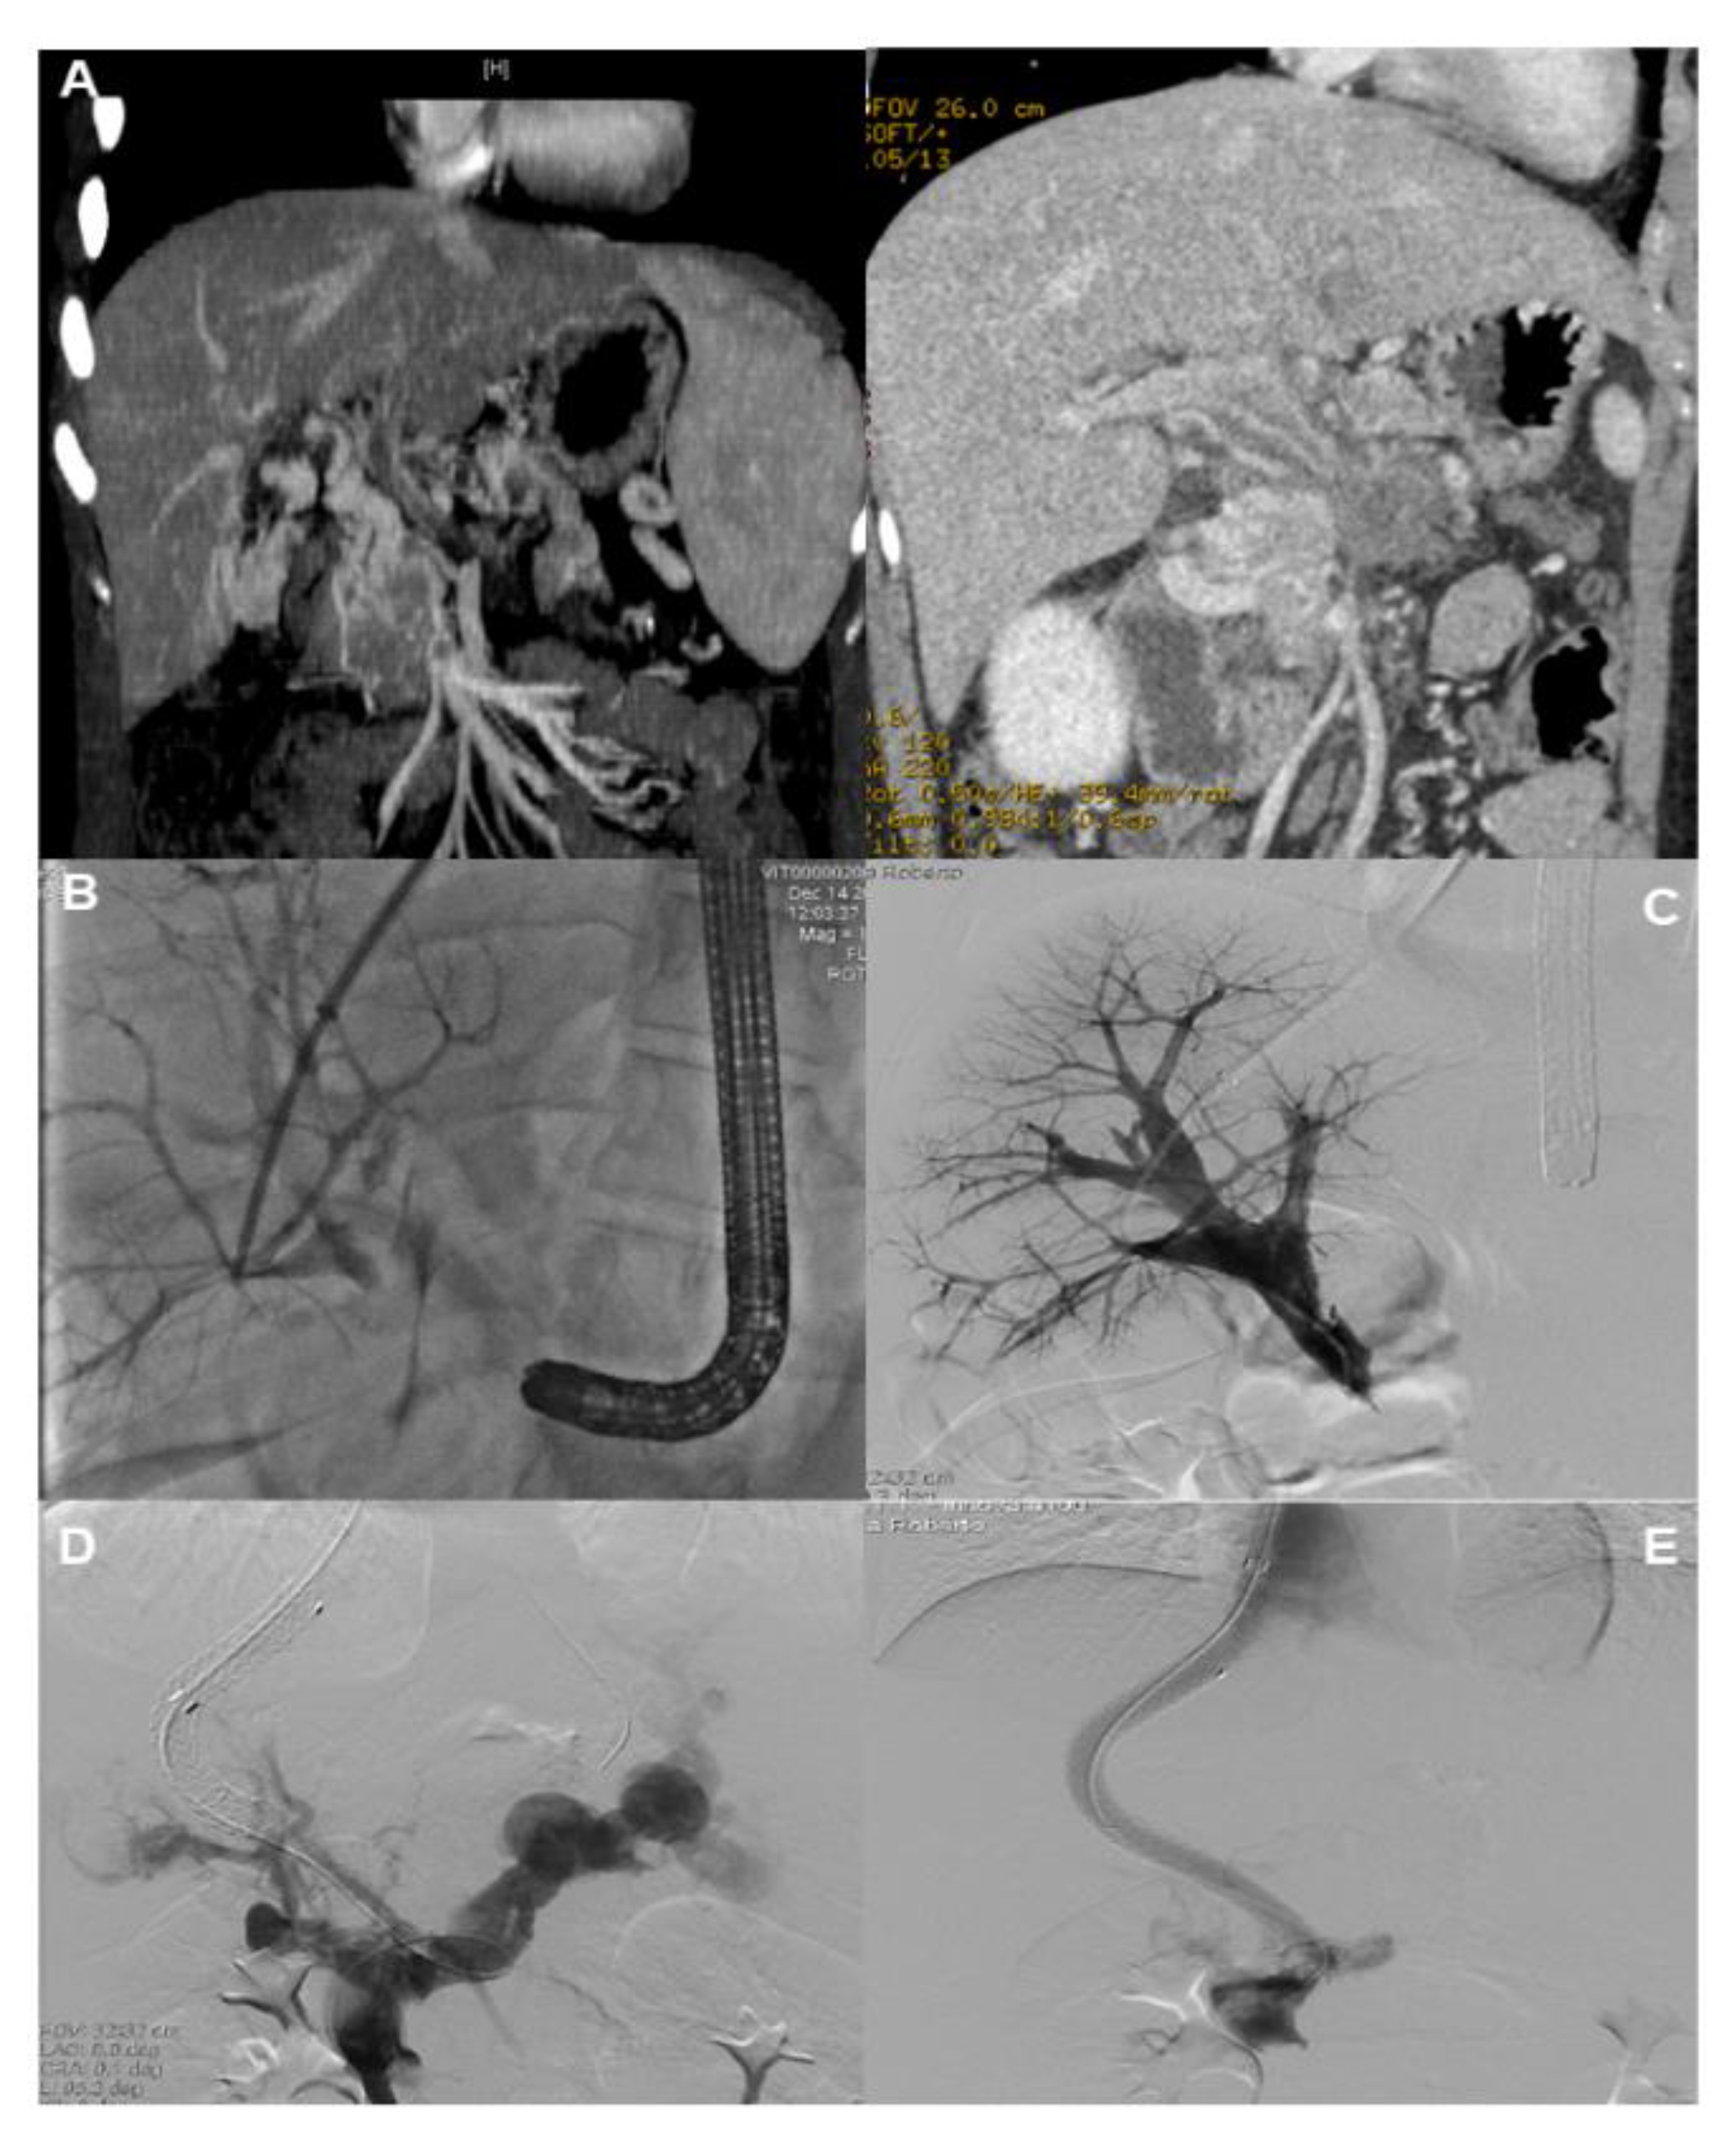

- Miraglia, R.; Maruzzelli, L.; Cannataci, C.; Gerasia, R.; Mamone, G.; Cortis, K.; Cimo, B.; Petridis, I.; Volpes, R.; Luca, A. Radiation exposure during transjugular intrahepatic portosystemic shunt creation in patients with complete portal vein thrombosis or portal cavernoma. Radiol. Med. 2020, 125, 609–617. [Google Scholar] [CrossRef]

- Chen, Y.; Ye, P.; Li, Y.; Ma, S.; Zhao, J.; Zeng, Q. Percutaneous transhepatic balloon-assisted transjugular intrahepatic portosystemic shunt for chronic, totally occluded, portal vein thrombosis with symptomatic portal hypertension: Procedure technique, safety, and clinical applications. Eur. Radiol. 2015, 25, 3431–3437. [Google Scholar] [CrossRef]

- Entezari, P.; Riaz, A.; Thornburg, B.; Salem, R. Percutaneous Ultrasound-Guided Superior and Inferior Mesenteric Vein Access for Portal Vein Recanalization-Transjugular Intrahepatic Portosystemic Shunt: A Case Series. Cardiovasc. Intervent. Radiol. 2021, 44, 496–499. [Google Scholar] [CrossRef]

- Steffen, D.A.; Najafi, A.; Binkert, C.A. Safety of Percutaneous Transmesenteric and Transsplenic Access for Portosystemic Shunt Creation in Patients with Portal Vein Obstruction: Single-Center Experience and Review of Literature. Cardiovasc. Intervent. Radiol. 2023, 46, 1401–1406. [Google Scholar] [CrossRef]

- Thornburg, B.; Desai, K.; Hickey, R.; Hohlastos, E.; Kulik, L.; Ganger, D.; Baker, T.; Abecassis, M.; Caicedo, J.C.; Ladner, D.; et al. Pretransplantation Portal Vein Recanalization and Transjugular Intrahepatic Portosystemic Shunt Creation for Chronic Portal Vein Thrombosis: Final Analysis of a 61-Patient Cohort. J. Vasc. Interv. Radiol. 2017, 28, 1714–1721. [Google Scholar] [CrossRef]

- Klinger, C.; Riecken, B.; Schmidt, A.; De Gottardi, A.; Meier, B.; Bosch, J.; Caca, K. Transjugular portal vein recanalization with creation of intrahepatic portosystemic shunt (PVR-TIPS) in patients with chronic non-cirrhotic, non-malignant portal vein thrombosis. Z. Gastroenterol. 2018, 56, 221–237. [Google Scholar] [CrossRef]